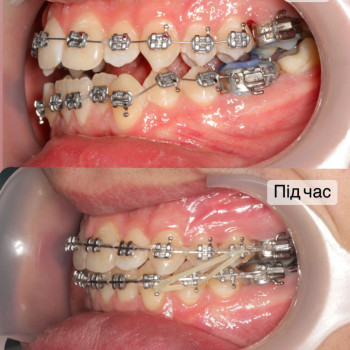

| Ортодонтия | |

| Установка брекетов | |

| Металлические брекеты | |

Якщо ти хочеш рівні зуби та красиву посмішку - тобі саме до нас!

Ми зробимо це на високому рівні!

А як саме наважитись на постановку брекетів?

Перший крок - це консультація ортодонта, Ви зможете дізнатись відповіді на запитання які Вас хвилюють. Перед постановкою брекетів усі зубки мають бути здорові, якщо ми бачимо карієс, його потрібно полікувати. Також потрібно зробити рентгенівські знимки для діагностики. За цей час, коли ми готуємо зуби до постановки брекетів, Ви зможете налаштуватись морально, звикнути з думкою що Ваша посмішка засяє новими барвами. На сьогоднішній час носіння брекетів являється престижним!